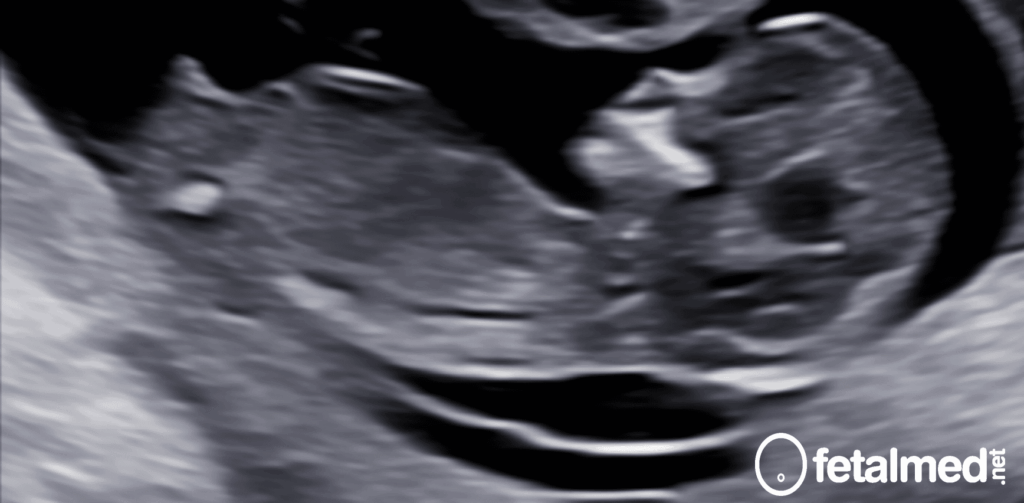

Ítens que devem ser observados na medida do Comprimento Cabeça-Nádegas (CCN). Fonte: Instagram Fetalmed Escola.

5. A imagem deve ser obtida no plano sagital médio

Perfil, coluna e nádega são visíveis

Costelas, estômago e coração não devem ser vistos neste plano.